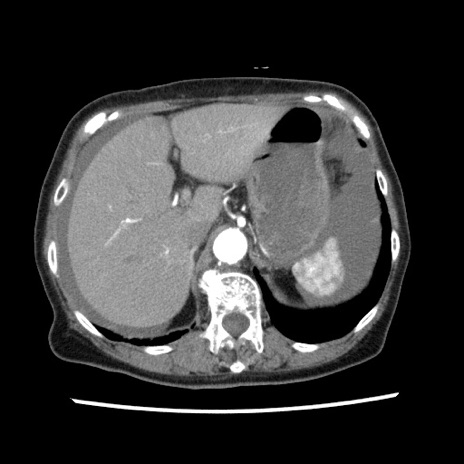

症例1(横断像)

【症例】80歳代女性

【主訴】腹痛

【現病歴】8時間前から腹痛あり来院。

【既往歴】糖尿病、脂質異常症、子宮体癌にて子宮全摘術

【身体所見】意識清明・会話良好だが腹痛で苦悶様、全腹部にわたって反跳痛と圧痛あり

【データ】WBC 13600、CRP 0.14、LDH 224、CK 90